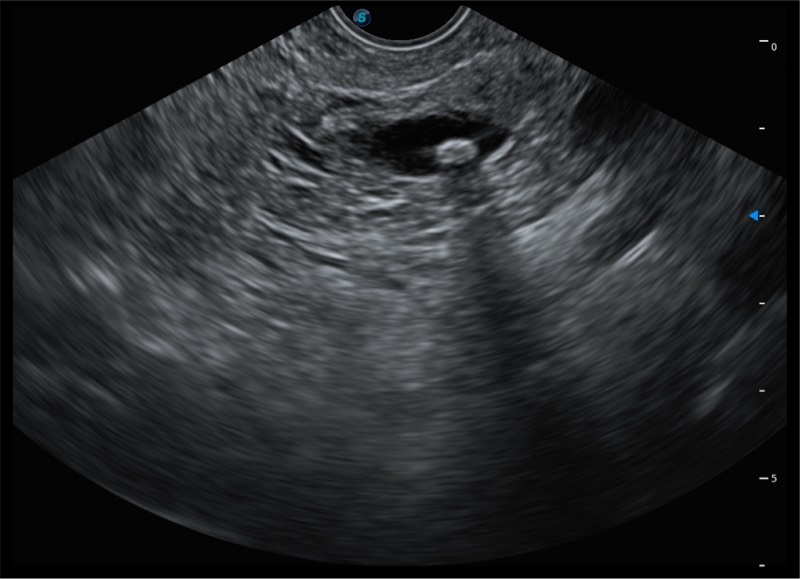

搭载百万级CMOS成像技术

及自主研发凸阵换能器,

可呈现优质的内镜和超声画面

基于二十年的超声技术积累,诸侯快讯官网提供了最新一代的独立超声主机,在提供高质量图像的同时满足多学科使用。具备常见多普勒技术并提供弹性成像、声学造影等高端影像技术。新一代传感器具有更强的抗干扰能力并减少图像伪影。

4-12MHZ宽频输出